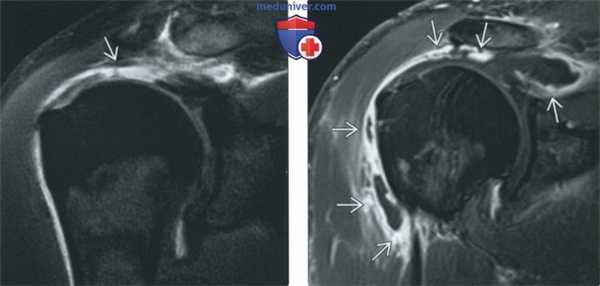

(Слева) Корональная Т1 FS МР-артрограмма: определяется разрыв всей толщины сухожилия надостной мышцы. У этого пациента в течение двух недель после артрографии имел место интенсивный болевой синдром и он вернулся для выполнения МРТ без КУ и с внутривенным КУ.

(Справа) Корональная Т1 FS МРТ, этот же пациент: визуализируется очаговое утолщение синовиальной оболочки, указывающее на выраженный синовит. В полученных чрескожно и открытым доступом образцах жидкости признаков инфекции не выявлено. ЦРБ был повышен, при нормальной СОЭ. Окончательный диагноз: «асептический синовит вследствие инъекционной артрографии».

Синовиальная оболочка выстилает влагалища сухожилий и суставные сумки, также как и суставы. Так как контрастное вещество экскрети-руется всей синовиальной оболочкой, сумки и сухожильные влагалища, как и суставы будут контрастированы. Это создает трудности в дифференциации, например, между малым разрывом вращательной манжеты плеча, приводящим к экстравазации контраста в подакромиальную/поддельтовидную сумку, и случаем тендинита и бурсита с контрастированием и сумки, и сустава.